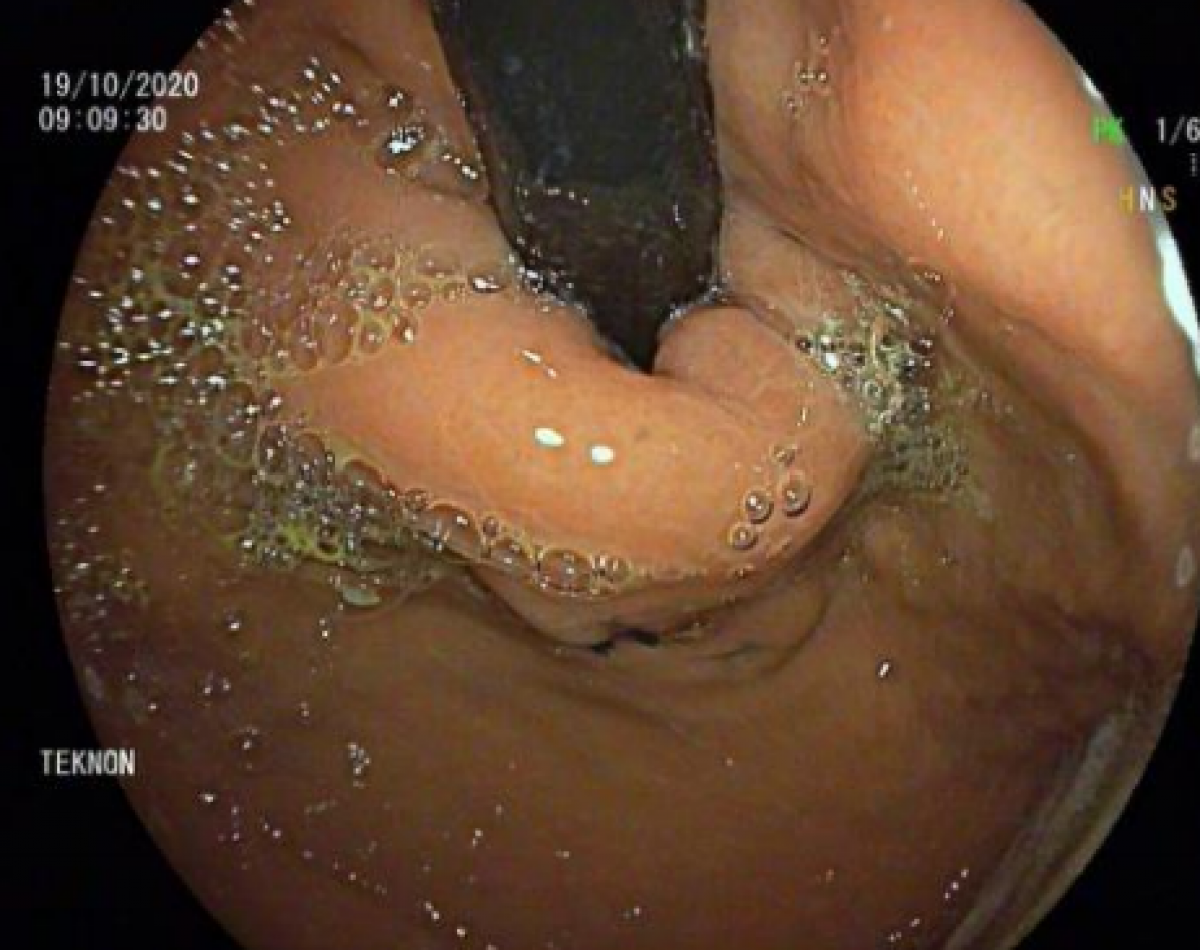

8 meses post TIF 1 BEC

Foto Pre TIF BEC

Foto antes de la operación (Centro Médico Teknon)

Foto después de la operación (Centro Médico Teknon)